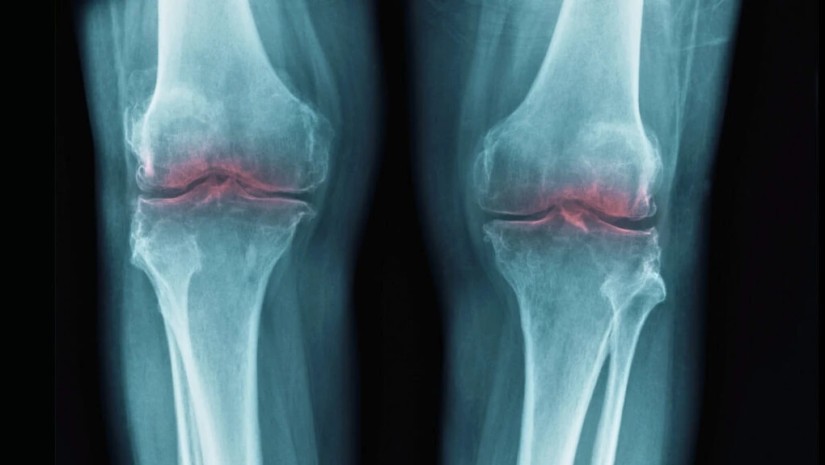

სტენფორდის უნივერსიტეტის მიერ თაგვებზე ჩატარებული კვლევით დადგინდა, ხრტილების დაკარგვა, რომელიც ასაკთან ერთად მოდის, გამოწვეულია ერთი ცილით. აღმოჩენა მიუთითებს მკურნალობის მეთოდებზე, რომლებმაც შეიძლება ერთ მშვენიერ დღეს ხანდაზმულებში აღადგინოს მოძრაობის უნარი და შეამსუბუქოს დისკომფორტი.

ამან მეცნიერები აიძულა განეხილათ, შესაძლოა თუ არა 15-PGDH ჩართული იყოს ოსტეოართრიტში — დაავადებაში, რომელშიც სახსრებზე დატვირთვა განაპირობებს ხრტილში კოლაგენის დაშლას, რაც ანთებას და ტკივილს იწვევს.

ხანდაზმულ თაგვებზე ჩატარებულ ცდებში, 15-PGDH ინჰიბიტორის (მბლოკავი) შეყვანის შემდეგ, მუხლის გაცვეთილი ხრტილი კვლავ გასქელდა. ახალგაზრდა თაგვებზე ჩატარებულ ასეთივე ცდებში, ინჰიბიტორმა ისინი დაიცვა ტრავმით გამოწვეული ოსტეოართრიტის ჩვეულებრივი ეფექტებისგან.

ასეთივე ექსპერიმენტი სცადეს იმ ადამიანებისგან აღებული ქსოვილების ნიმუშებზე, რომლებსაც მუხლის ჩანაცვლების ოპერაცია ჰქონდათ ჩატარებული. აქაც დაფიქსირდა აღდგენის მკაფიო ნიშნები, ხრტილი გახდა უფრო მაგარი და აღენიშნებოდა ანთების მხოლოდ მცირე ნიშნები.